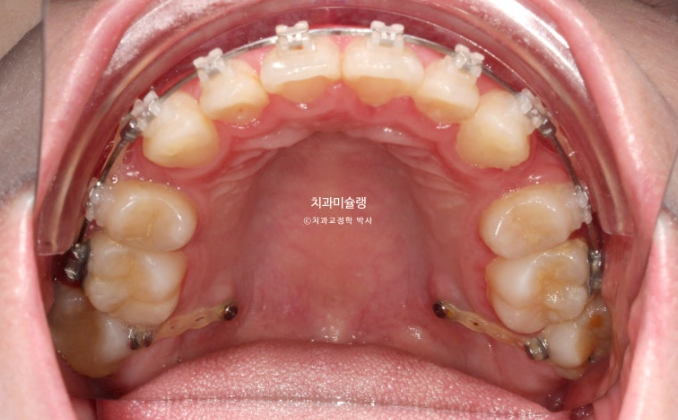

가위교합의 개선을 위해서는 입천장에 교정용 나사가 필요합니다.

앞니를 최대한 뒤로 많이 넣어야 하는 상황이라서 입천장뿐 아니라 볼쪽에도 교정용 나사를 심고 진행했습니다.

파란 화살표 큰어금니가 입천장쪽으로 들어오면서 가위교합이 해소가 되었습니다.

파란 화살표 부분의 가위교합이 개선이 되면서 어금니 교합은 물샐틈 없는1급 교합관계를 보입니다.